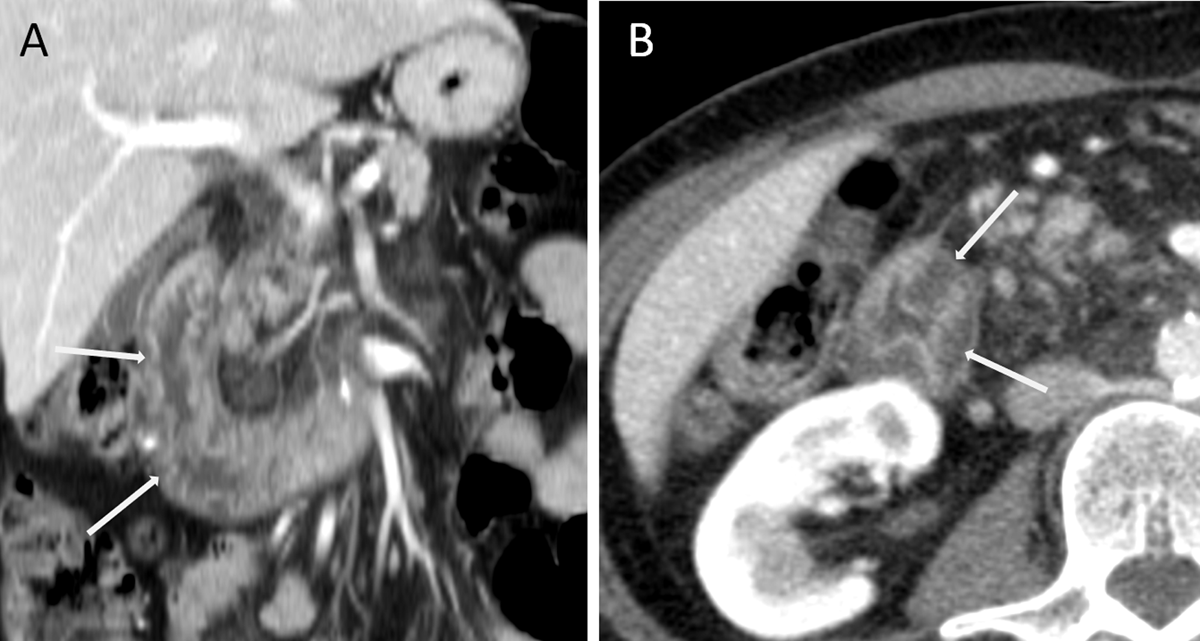

A 54-year-old female was hospitalized for severe hyponatremia and electrolytic troubles. She had increasing fatigue, loss of appetite and lower limbs edema. Abdominal contrast-enhanced computed tomography (CT) revealed circumferential parietal thickening of the proximal duodenum, with low attenuation of the submucosal layer (Figure 1A and B, arrows).

Figure 1

There was no fat infiltration nor vessel hypertrophy suggestive of inflammatory bowel disease. Endoscopic exploration showed mucosal ulcerative lesion and the biopsy revealed focal lymphangiectasias in the submucosal layer. Clinical presentation associated with biological and histological findings suggested the diagnosis of protein-losing enteropathy (PLE). Human serum albumin scintigraphy (Tc99m) confirmed the diagnosis and showed loss of tracker in the duodenum.